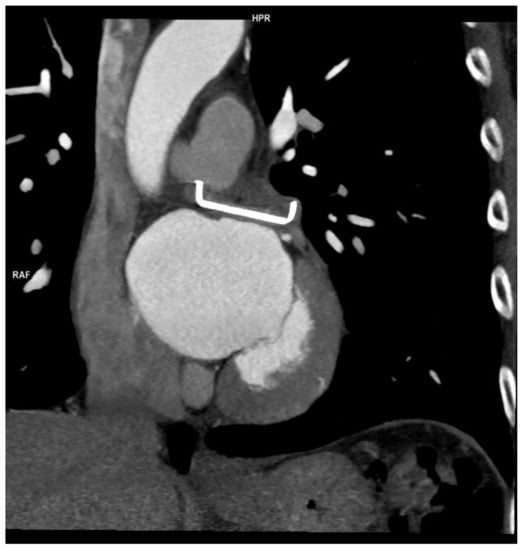

2.2. LAAO-T Procedure